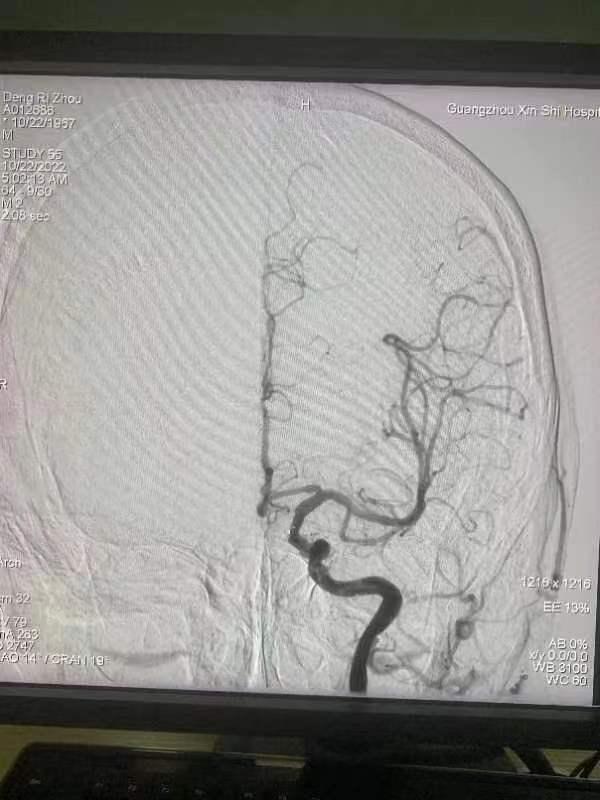

得到邓先生家属同意后,凌晨1点50分,卒中中心介入团队便为邓先生开展桥接介入手术。经验丰富的黄副主任仅用了不到1小时,便为邓先生打通血管,恢复血流。

然而好事多磨,邓先生的血流恢复后,短时间内却再次堵塞。原来是邓先生左侧颈内动脉有重度狭窄,狭窄约80%,所以就算血流恢复也很快再次堵塞。

为确保手术效果,黄副主任当机立断,在经皮颅动脉取栓的基础上,为邓先生多做两步:放入球囊扩张血管、植入支架,一气呵成无缝衔接,解决邓先生卒中问题的同时,也最大限度保障了术后康复效果。